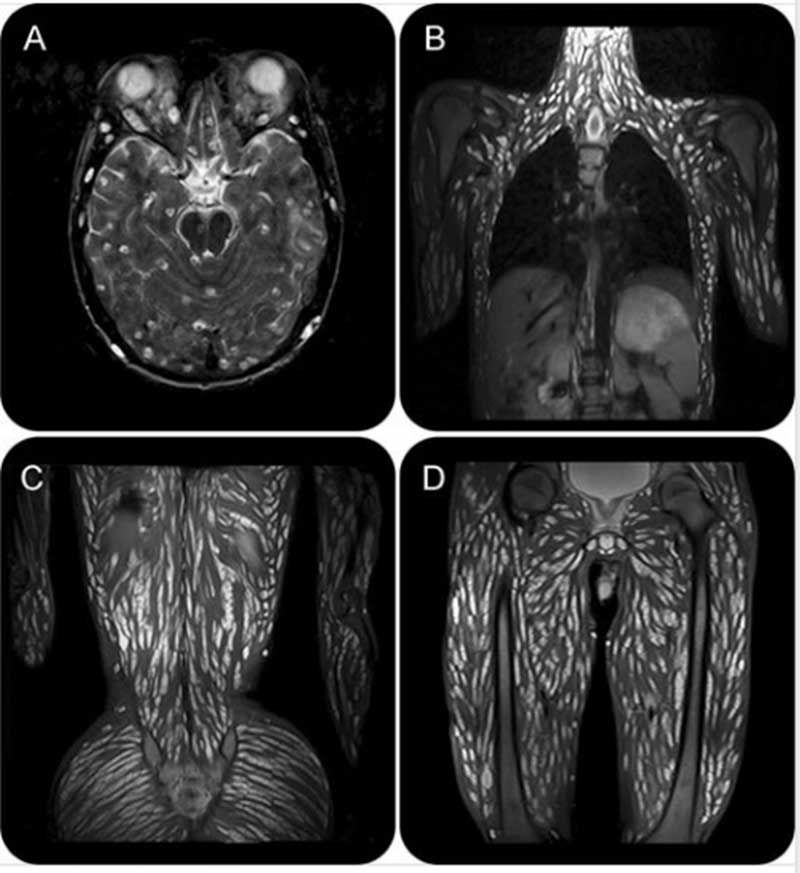

ศูนย์วิจัยปรสิตเผยภาพพยาธิตืดหมู  กระจายเต็มตัวผู้ป่วยวัย 18 ปี หลังปวดหัว อาเจียน ชัก

วันที่ 12 มิถุนายน 2563 เพจเฟซบุ๊ก "PDRC ศูนย์วิจัยโรคปรสิต สำนักวิชาแพทยศาสตร์ มหาวิทยาลัยเทคโนโลยีสุรนารี" โพต์ภาพเอกซเรย์เอ็มอาร์ไอผู้ป่วยวัย 18 ปีรายหนึ่งที่มาโรงพยาบาลด้วยอาการปวดศีรษะอาเจียน ชักและประสาทสัมผัสเปลี่ยนแปลง

ซีสต์พยาธิตืดหมูกระจายเต็มตัวเลย จากภาพนี้ จะเห็นจุดสีขาวๆ ซึ่งเป็นระยะตัวอ่อน cysticercus ของพยาธิตืดหมู กระจายเต็มไปหมด

ผู้ป่วยอายุ 18 ปี ไปโรงพยาบาลด้วยอาการปวดศีรษะอาเจียน ชัก และประสาทสัมผัสที่เปลี่ยนแปลง

แพทย์ตรวจ MRI พบซีสต์จำนวนมากในเนื้อเยื่อสมอง ศีรษะ กล้ามเนื้อ คอ ผนังหน้าอก ผนังหน้าท้อง กล้ามเนื้อข้างกระดูกสันหลัง สะโพก กระดูกเชิงกราน และกล้ามเนื้อแขนขา (รูป) (Rajesh Jawale & Dhananjay Duberkar, 2015)

ผู้ป่วยได้รับยาสเตียรอยด์และยากันชักและมีการฟื้นตัวดีขึ้น ผู้ป่วยได้รับการวินิจฉัยว่าเป็น disseminated cysticercosis

การได้รับเชื้อนี้ เกิดจากการกินไข่พยาธิที่ปนเปื้อนในผัก ผลไม้ น้ำ หรือดินที่ติดมากับมือแล้วไม่สะอาด

Rajesh Jawale, Dhananjay Duberkar. Disseminated cysticercosis. Neurology Jan 2015, 84 (3) 327; DOI: 10.1212/WNL.0000000000001152